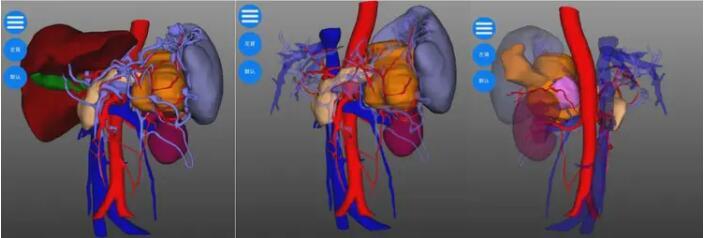

由于患者瘤体巨大,侵及周围脾、肾上腺、结肠、胃、十二指肠等多个脏器器官,手术难度极高,翟博教授随即请科室主任谭刚教授会诊,基于对患者病情分析及为降低手术风险,完善胰腺三维成像,得以精准定位肿瘤位置及周围血管分布,精准规划手术流程。

谭刚教授仔细研究了赵大娘的病情,认为肿瘤虽然涉及多个脏器,但尚未发生远处转移,为挽救患者生命,谭刚教授毅然决定开腹探查,以期为患者争取最后的治疗机会,经过周密的术前准备,赵大娘躺到了手术台上。术中探查可见胰体尾肿物,累及脾门、侵及结肠脾曲,脾动静脉、胃底及十二指肠,在谭刚教授、翟博教授两位主任的精密合作下,经过3个多小时的艰苦奋战,为赵大娘施行了“根治性胰体尾切除、脾切除、结肠脾曲切除、胃十二指肠修补术,左侧肾上腺切除”的多器官联合切除,患者术后顺利返回病房。目前患者恢复非常顺利,已康复出院。出院时,赵大娘家属激动地表示:“真的没想到这么大的肿瘤还有根治的希望,在切除了这么多器官后,术后还恢复得这么快,感谢普外二团队给了我老伴第二次生命!”。